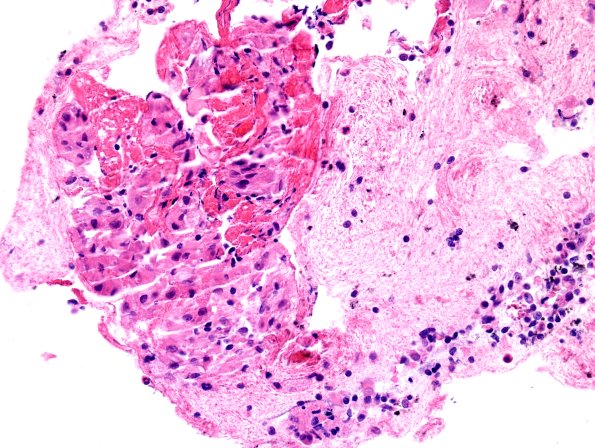

2C2,3 An endobronchial ultrasound-guided fluoroscopy assisted fine needle aspiration of a lung lesion showed non-necrotizing granulomatous inflammation without fungal or AFB organisms. (H&E)